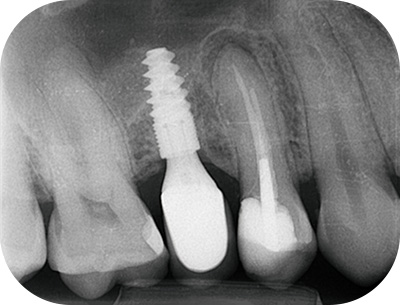

prémolaire, radio pré-opératoireFig. 05 : radio pré-opératoire.

prémolaire, radio per-opératoire cone en placeFig. 06 : radio per-opératoire cone en place.

radio per-opératoire cone ajustéFig. 07 : radio per-opératoire cone ajusté.

Radio per-opératoire après WVCFig. 08 : radio per-opératoire après WVC.